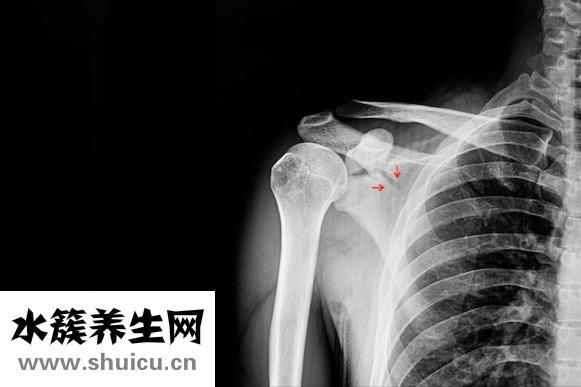

肋骨骨折怎么也得養一個月吧,不然是很疼的。日前郭富城現身電影節的時候透露在拍攝電影《內幕》時,因拍攝而導致拉傷肋骨,事關影片中要將自己吊威亞至很高的位置,而且還是旋轉的拍攝...